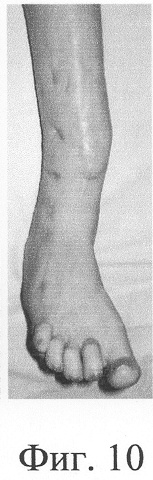

Больная П., 42 лет, поступила для оперативного лечения с диагнозом «атрофические ложные суставы обеих большеберцовых костей; сросшийся с укорочением 5 см перелом левой бедренной кости, хронический остеомиелит левой бедренной кости, фаза ремиссия; посттравматическая невропатия правого малоберцового нерва». В анамнезе – накостный, а затем дважды внеочаговый остеосинтез левой большеберцовой кости с исходом в ложный сустав; 4 операции внеочагового остеосинтеза правой большеберцовой кости, в том числе с костной пластикой; сроки фиксации в аппарате от 5 до 10 мес. Результат не достигнут: с обеих сторон сформировались ложные суставы (фиг.8-11 – клинические и фиг.12-15 – рентгенологические данные до лечения по предложенному методу).